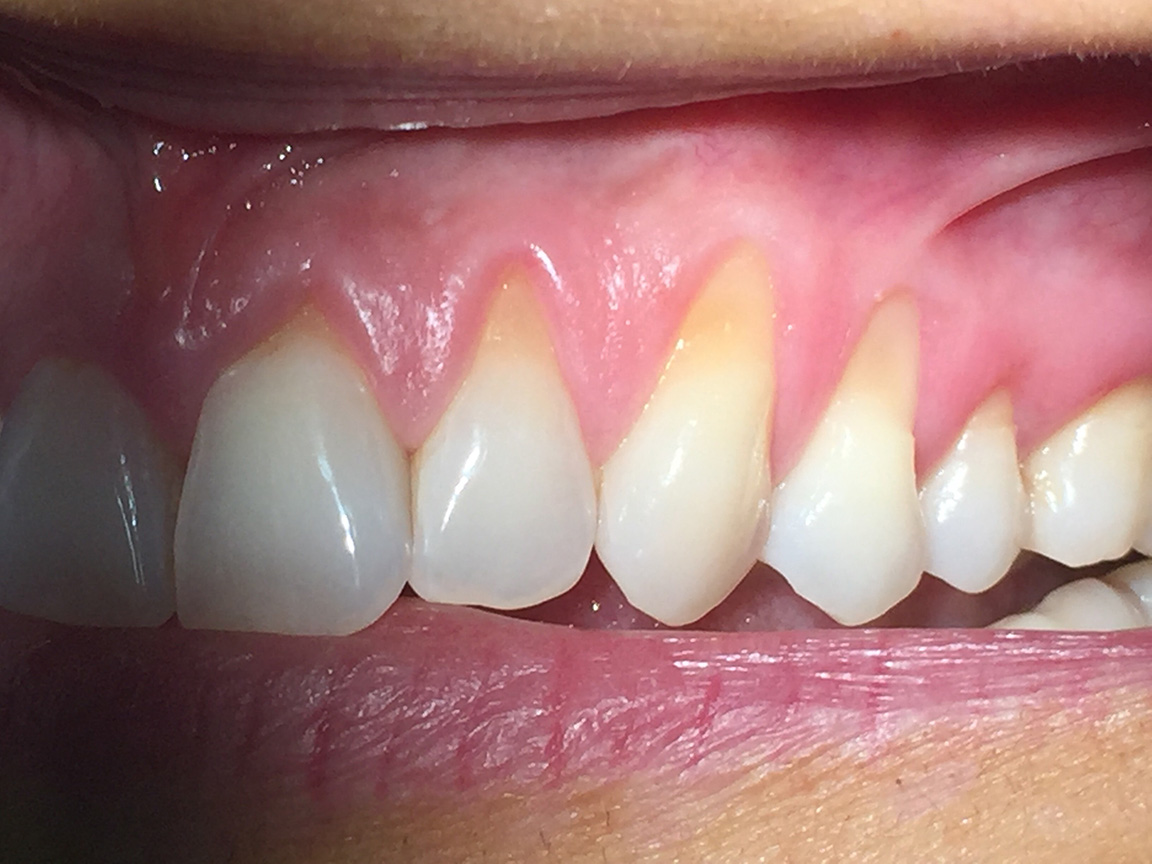

Correzione SIMULTANEA di recessioni multiple su quadrante sup sx con tecnica bilaminare di chirurgia mucogengivale, con innesto di connettivo autologo.

Photogallery: